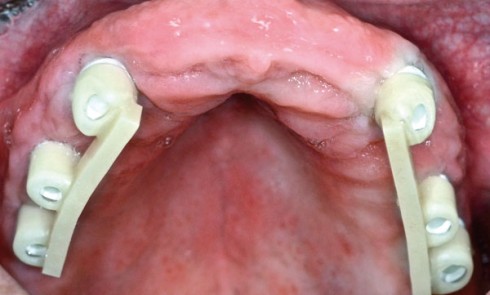

Article réservé à nos abonnés Prothèses implanto-stabilisées : clinique

DÉCISION THÉRAPEUTIQUE Après la période d’ostéointégration, la troisième étape clinique peut débuter. Concernant ce patient, le choix de PMPIS, et...

Article réservé à nos abonnés Prothèses implanto-stabilisées sur piliers télescopiques : étapes de laboratoire

Le patient est porteur d’une prothèse complète bimaxillaire mucoportée réalisée grâce à la piézographie qui a délivré toutes les informations...